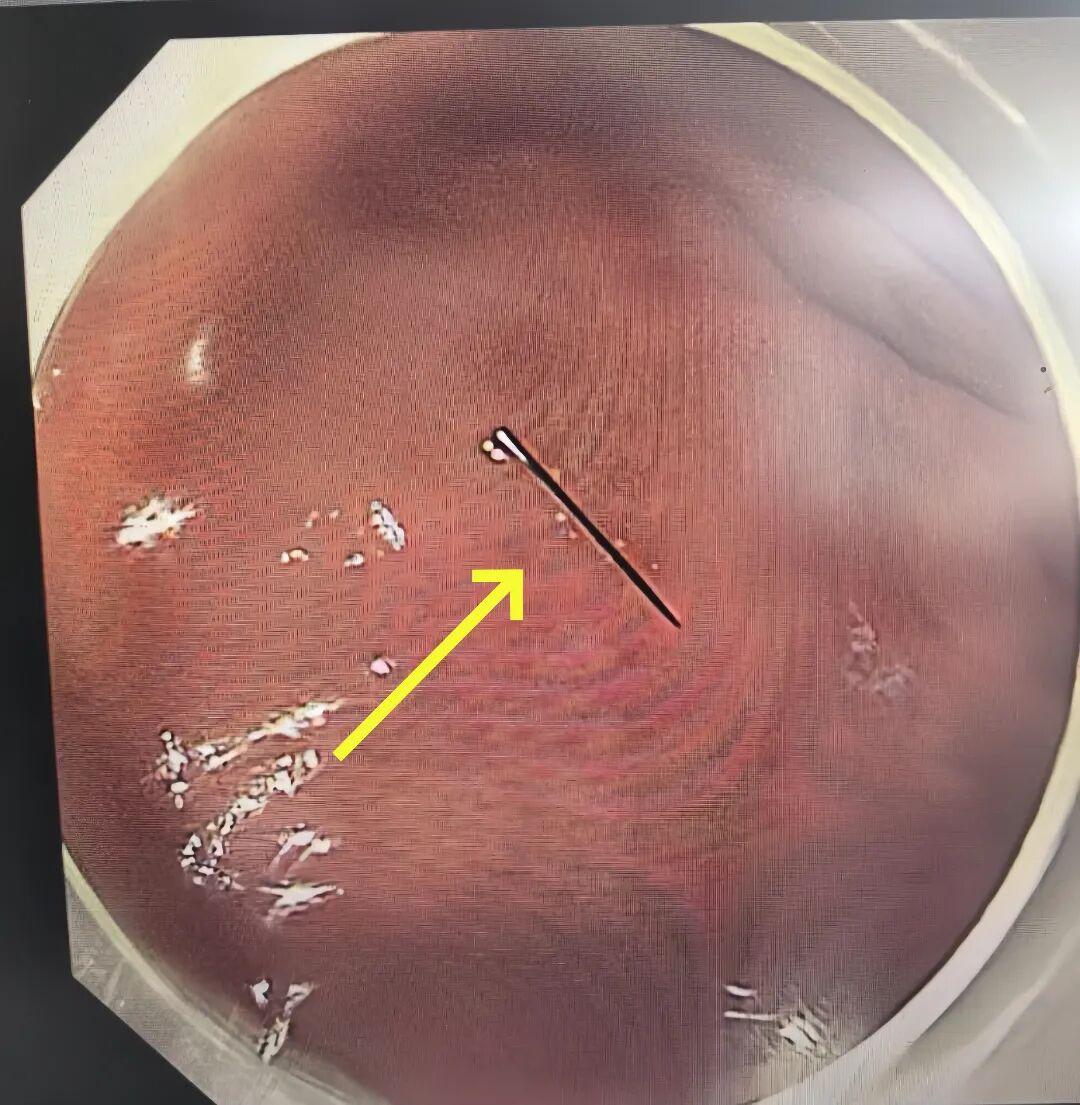

凌晨3点,术前准备就绪,一场全麻下胃镜异物取出术正式开始。凭借丰富的儿童内镜经验,手术仅用10余分钟就顺利完成,那截约1 厘米长的断针被完整取出。

万幸的是,断针尚未刺破胃黏膜、未造成出血损伤。当医生将取出的断针展示在家人面前时,一直悬着的心终于落地。